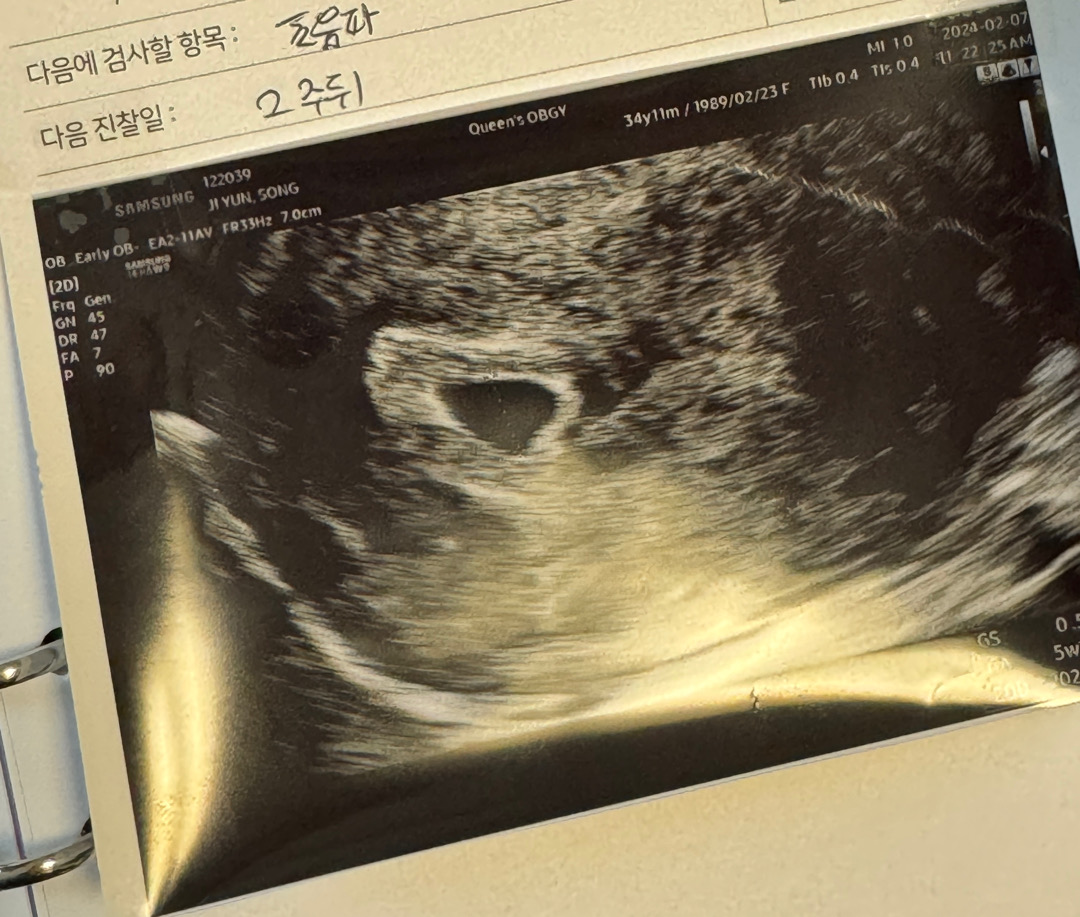

어제 초음파보고왔어요🤍

5주라고해요! 초음파 사진 어떤가용? 선생님은 느낌 좋다고 해주셔서 맘이 놓였지만 유산을 3번하고 4번째 자연임신된거라 불안감이 너무 커요🥹응원해주세요🤍